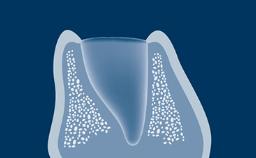

O uso de próteses dentárias implantossuportadas para substituir dentes perdidos resultou em um foco renovado nas técnicas de extração, particularmente na zona estética. A remoção do dente sem danificar o alvéolo pode facilitar a cicatrização pós-operatória, as técnicas de preservação do rebordo e a subsequente instalação do implante. Este módulo descreverá as técnicas para remover um dente condenado, com a instalação do implante em mente.

- descrever os efeitos biológicos da perda dentária no processo dentoalveolar